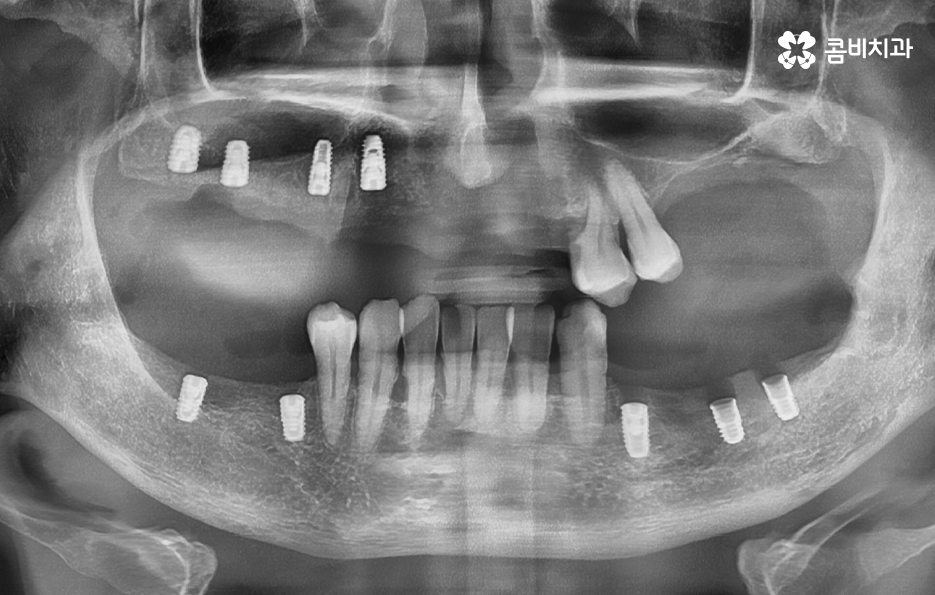

65세이상 임플란트 건강보험 혜택의 주된 내용은 65세이상 임플란트 개수 평생 2개까지 보험 적용 가능이라는 점으로 본인 부담률 30% 한하여 환자가 치료비를 부담하면 되기 때문에 경제적으로 상당히 큰 혜택이라고 할 수 있어요

다만 여기서 주의해야 할 점은 65세이상 임플란트 개수 평생 2개까지 혜택을 받을 수 있다는 점에서 되도록 자연치아의 건강을 잘 유지하면서 필요한 시점에 혜택을 잘 활용하는 것이 중요하겠고 노년기에 치료를 받아야 한다는 점에서는 잇몸 뼈의 상태 및 전신건강까지 잘 고려할 수 있는 시스템이 잘 갖춰지고 경험 많은 치과의사와 함께 치료 계획을 잘 세워야 하며 건강보험 혜택에서는 뼈이식이나 상악동거상술, 보철물의 변경 같은 추가적인 사항에 대해서는 별도의 비용으로서 치료비를 납부해야 하므로 각 환자분들에게 적합한 치료 계획에 대해 잘 이해하여 치료비 예산을 잘 계획하실 필요가 있었어요.

임플란트는 단순 치아 대체물이 아니고, 노년기 전신 건강과 영양 유지, 삶의 질을 지키는 치료로서 씹는 기능이 회복되면 식사량이 늘고, 영양 흡수가 좋아지고, 면역력도 안정되면서 전신 건강에도 긍정적인 변화가 생길 수 있기 때문에 치아의 상실에 대해 가볍게 여기지 마시고 기대수명을 고려한다면 60대는 물론이며 70대 혹은 그 이후에도 충분히 장기적인 관점으로 임플란트 치료를 바라보고 활용 및 관리하시길 바라고 있어요